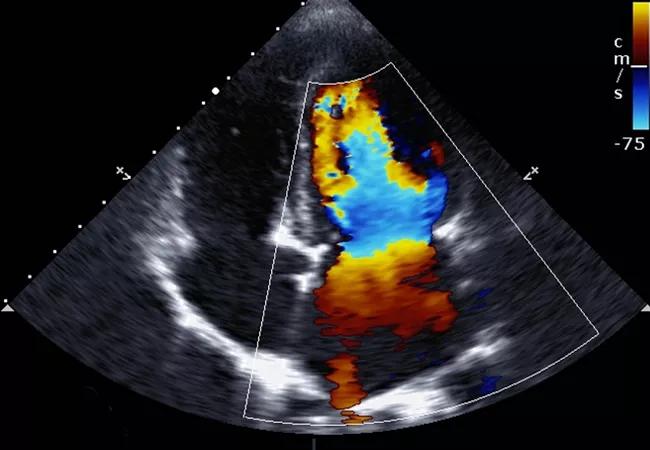

New research presented by Dr. Rosenthal at the American College of Surgeons Clinical Congress 2017 suggests a bariatric surgical procedure and the weight loss that follows it can reestablish the heart to its natural shape and function.

When confronted with fat, the heart has to pump harder to move blood through the body, which causes the heart to grow bigger. Unlike other muscles in the body, the larger the heart muscle, the less effectively it performs.

After one year, 25 patients (49%) showed normal left ventricular geometry. Specifically, the left atrial mass (229 ± 82.1 vs. 193.2 ± 42.5, P < 0.01, 95% CI) and the left ventricular end diastolic volume (129.4 ± 53 vs. 96.4 ± 36.5, P = 0.01, 95% CI) showed significant modification following the procedure. There was also significant modification in the interventricular septal thickness (P = 0.01, 95% CI) and relative wall thickness (< 0.01, 95% CI) following surgery.

“We were encouraged to see the heart return to its normal geometry after bariatric surgery and weight loss,” Dr. Rosenthal says. “There is a direct positive correlation between the decrease in BMI and the improvement of the left ventricular structure.”